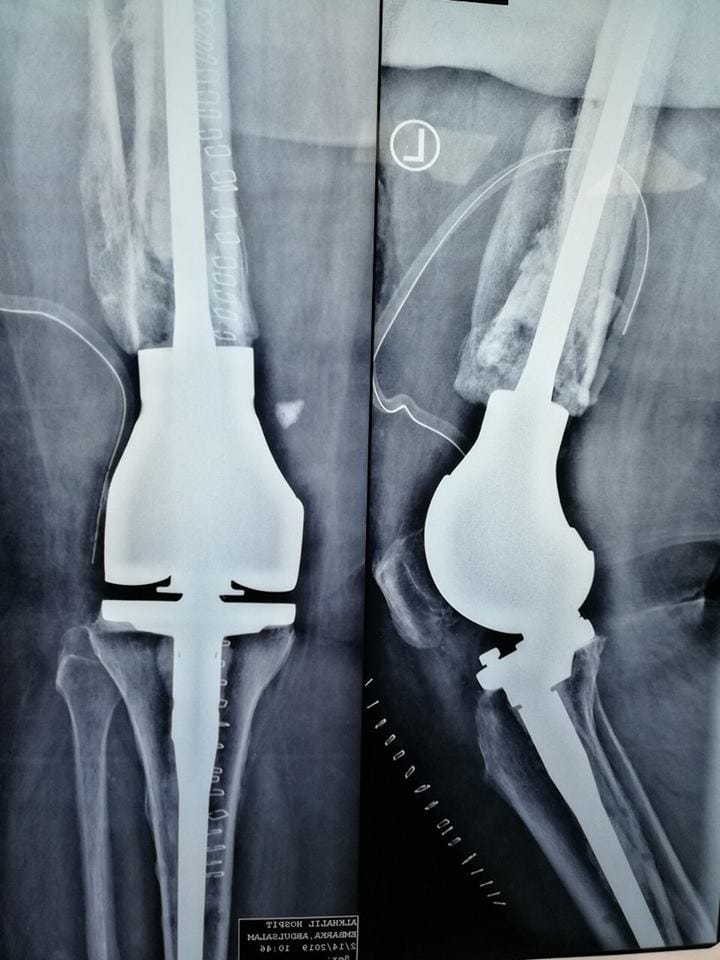

كللت العملية التي أجراها استشاري جراحة العظام والمفاصل الدكتور” حسين الرجباني” بمستشفى الخليل والفريق الطبي المرافق له لزراعة مفصل من نوع خاص لمريضة تبلغ من العمر “68 “عام تعرضت إلى حادث سير من سنوات أدى إلى كسر في عظمة الفخذ فوق الركبة، تم علاجها في إحدى المراكز المتخصصة في السابق بالتثبيت الخارجي أدى إلى التأم الكسر بوضعيه غير طبيعية مع وجود احتكاك متقدم في الركبة وأصبحت تعاني من صعوبة في الحركة والمشي.

وبعد عرض المريضة على الدكتور” الرجباني”، قرر إجراء عملية للمريضة وتم التنسيق باستجلاب مفصل خاص لها من شركة “Link” الألمانية الرائدة في هذا المجال، وأجريت لها العملية التي كللت بالنجاح، وأكد الدكتور بأن حالتها في تحسن ملحوظ بعد إحالتها لقسم العلاج الطبيعي وخضوعها لعدة جلسات وبدأت في تحرك بشكل طبيعي ولاتشتكي من الألم السابقة ، وأشاد بالجهود التي بذلها الفريق الطبي المرافق له من اجل نجاح العملية.

كما أعلن”الرجباني”، بأن هذا النوع من الجراجات في مجال العظام تجرى لأول مره في ليبيا، وتجرى بالمراكز المتقدمة في أوروبا.